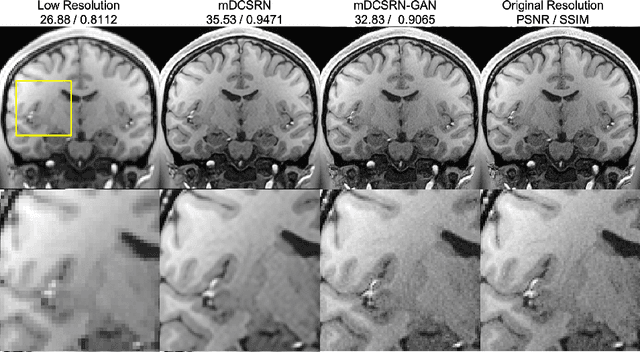

Abstract:High-resolution (HR) magnetic resonance imaging (MRI) provides detailed anatomical information that is critical for diagnosis in the clinical application. However, HR MRI typically comes at the cost of long scan time, small spatial coverage, and low signal-to-noise ratio (SNR). Recent studies showed that with a deep convolutional neural network (CNN), HR generic images could be recovered from low-resolution (LR) inputs via single image super-resolution (SISR) approaches. Additionally, previous works have shown that a deep 3D CNN can generate high-quality SR MRIs by using learned image priors. However, 3D CNN with deep structures, have a large number of parameters and are computationally expensive. In this paper, we propose a novel 3D CNN architecture, namely a multi-level densely connected super-resolution network (mDCSRN), which is light-weight, fast and accurate. We also show that with the generative adversarial network (GAN)-guided training, the mDCSRN-GAN provides appealing sharp SR images with rich texture details that are highly comparable with the referenced HR images. Our results from experiments on a large public dataset with 1,113 subjects showed that this new architecture outperformed other popular deep learning methods in recovering 4x resolution-downgraded images in both quality and speed.

Abstract:High-resolution (HR) magnetic resonance images (MRI) provide detailed anatomical information important for clinical application and quantitative image analysis. However, HR MRI conventionally comes at the cost of longer scan time, smaller spatial coverage, and lower signal-to-noise ratio (SNR). Recent studies have shown that single image super-resolution (SISR), a technique to recover HR details from one single low-resolution (LR) input image, could provide high-quality image details with the help of advanced deep convolutional neural networks (CNN). However, deep neural networks consume memory heavily and run slowly, especially in 3D settings. In this paper, we propose a novel 3D neural network design, namely a multi-level densely connected super-resolution network (mDCSRN) with generative adversarial network (GAN)-guided training. The mDCSRN quickly trains and inferences and the GAN promotes realistic output hardly distinguishable from original HR images. Our results from experiments on a dataset with 1,113 subjects show that our new architecture beats other popular deep learning methods in recovering 4x resolution-downgraded im-ages and runs 6x faster.

Abstract:Magnetic resonance image (MRI) in high spatial resolution provides detailed anatomical information and is often necessary for accurate quantitative analysis. However, high spatial resolution typically comes at the expense of longer scan time, less spatial coverage, and lower signal to noise ratio (SNR). Single Image Super-Resolution (SISR), a technique aimed to restore high-resolution (HR) details from one single low-resolution (LR) input image, has been improved dramatically by recent breakthroughs in deep learning. In this paper, we introduce a new neural network architecture, 3D Densely Connected Super-Resolution Networks (DCSRN) to restore HR features of structural brain MR images. Through experiments on a dataset with 1,113 subjects, we demonstrate that our network outperforms bicubic interpolation as well as other deep learning methods in restoring 4x resolution-reduced images.